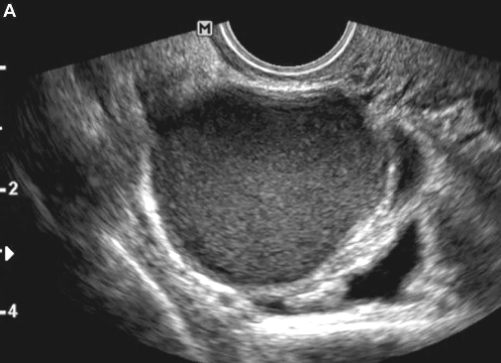

Paciente de 30 anos, G1P1 (C), veio ao consultório com queixas de cólicas de média intensidade no período catamenial há quatro anos, de caráter progressivo, associada à irregularidade menstrual. Sem métodos contraceptivos há dois anos. Traz consigo resultado de ultrassonografia que revela cisto em região ovariana, volumoso, uniloculado, com conteúdo tipo “vidro fosco” e ausência de vascularização ao Doppler.

Considerando o quadro acima, qual a melhor conduta?